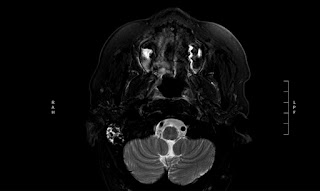

So. It’s not surprising that there is some weird shit going on in my brain. Check out the images from todays mri and CT.

Says I could have temporal lobe necrosis with edema which would explain recent memory difficulty

Dysfunction in the temporal lobe may cause dysfunction in the mind.